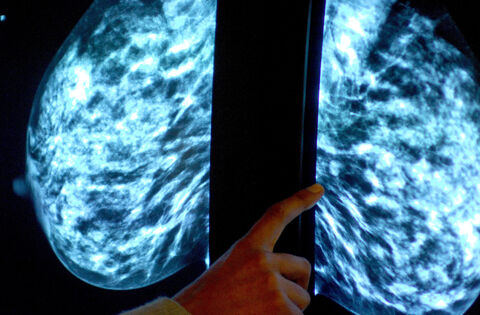

A number of issues around staffing are contributing to difficulties providing mammography services at Mayo University Hospital (MUH), according to a HSE manager.

The matter was raised at last week's Health Forum West by Castlebar-based Cllr Michael Kilcoyne who said Mayo women can no longer avail of a mammography service in the Castlebar Primary Care Centre and must travel to Galway instead. Cllr Kilcoyne said the BreastCheck service "has not been to Mayo for quite some time".

Area Health Manager Mary Warde said the MUH mammography service, which is normally provided at Castlebar Primary Care Centre, is currently experiencing staff shortages. The initial vacancy arose as a result of a retirement and to date the HSE has not been successful in filling the position. As a result, patients are being offered appointments at University Hospital Galway (UHG).